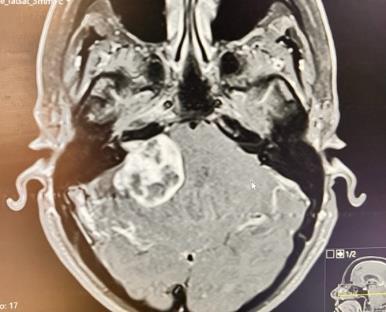

I was diagnosed with a large Vestibular Schwannoma brain tumour in September 2023. I’d had many years of symptoms including numbness of my face, balance issues and vertigo. For almost 3 years I went to doctors, yet my symptoms were ignored and I was told it was mental health related. It was my dentist who finally sent me for a scan.

When I was diagnosed and heard the words benign, I felt relief, as my husband and I have four young children and I needed to be around for them.

I had surgery to remove the tumour in April 2024, and after 14 hours on the operating table my husband received the call to tell him the surgery went well… Less than one hour later he got another call saying I hadn’t woken up and was going straight for a scan.

What they found then was a huge clot pressing on my brain stem. It totally blindsided everyone, even the professionals. They actually ended up getting a few neurosurgeons from London involved too. I think there were 5 in total. “It’s a very rare case” they said.